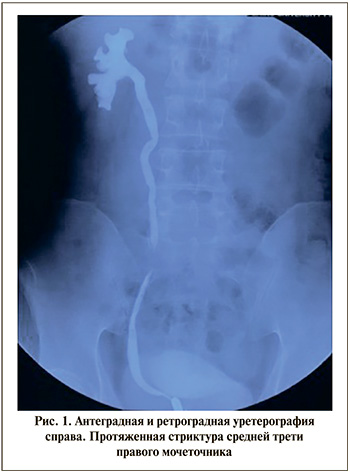

Техника операции. Всем больным выполнена лапароскопическая onlay-пластика протяженной стриктуры правого мочеточника аппендиксом. Операцию выполняли в положении на левом боку. Использовали четыре троакара, первый из которых устанавливали в правой подвздошной области по Хансону. После инсуфляции брюшной полости до 12 мм рт.ст. проводили еще три троакара: два по 6 мм по подключичной линии в подвздошной области и ниже реберной дуги, один 6 мм по задней аксиллярной линии. Далее мобилизовали восходящую толстую кишку и отводили ее медиально. С иссечением рубцовых тканей в забрюшинном пространстве идентифицировали мочеточник на протяжении верхней или средней трети. Максимально сохраняя неизмененные ткани, выделяли суженный участок, протяженность которого определяли несколькими способами. Предоперационно для этого одновременно выполняли антеградную и ретроградную уретерографию (рис. 1). Однако истинная протяженность дефекта мочеточника может быть большей, чем по данным рентгенографии. Наиболее эффективно использование ближней инфракрасной флуоресцентной визуализации для подтверждения длины сужения. Для этого внутривенно вводили индоцианин зеленый, уточняли зоны нормальной и плохой перфузии стенки мочеточника (рис. 2). При этом стенка нормального мочеточника интенсивно окрашивалась индоцианином, а рубцово суженный участок менял свой цвет незначительно. Далее рассекали его просвет на протяжении суженного участка, разрез продолжали на 1,0 см выше и ниже этой зоны. После этого еще раз определяли длину стриктуры с помощью мочеточникового катетера, заведенного в брюшную полость (рис. 3).